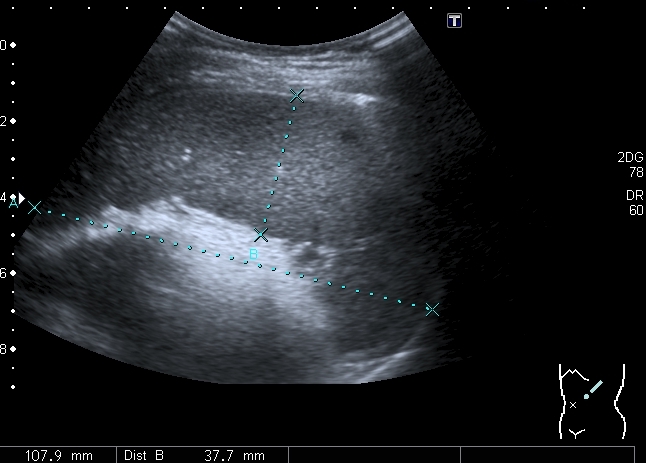

Девочка 13 лет, в течение 2-х недель температура до 38, СОЭ - 40 мм\ч, СРБ - 30.

На УЗИ: Учитывая клинику, лабораторные данные поставил гистиоцитарную инфильтрацию печени и селезёнки при генерализованной инфекции. Несколько раз встречался со схожими случаями, на фоне антибиотикотерапии изменения уходили. Но в данном случае девочка уже получала антибиотики в течение недели, на этом фоне не получено ни клинического , ни лабораторного улучшения, а на УЗИ очаги стали больше. Нужно ли расширять дифференциально -диагностический ряд? Ваши мнения

Имхо, по УЗ-семиотике - множественные небольшие абсцессы.

Мне нравится информация по данной патологии из видаровского "Клинического руководства по ультразвуковой диагностике в педатрии". Там данные изменения носят название очаговых поражений инфекционной этиологии (иерсиниоз, псевдотуберкулёз, токсокароз, хламидиоз и др.). Но инфекционисты, проведя ИФА с очень скудным набором диагностикумов и получив отрицательный результат, так же говорят, что это "не их".

В наше время тактика ведения абсцессов немного изменилась - крупные абсцессы (более 3 см в диаметре) дренируют, мелкие (менее 3 см) лечат антибиотиками.